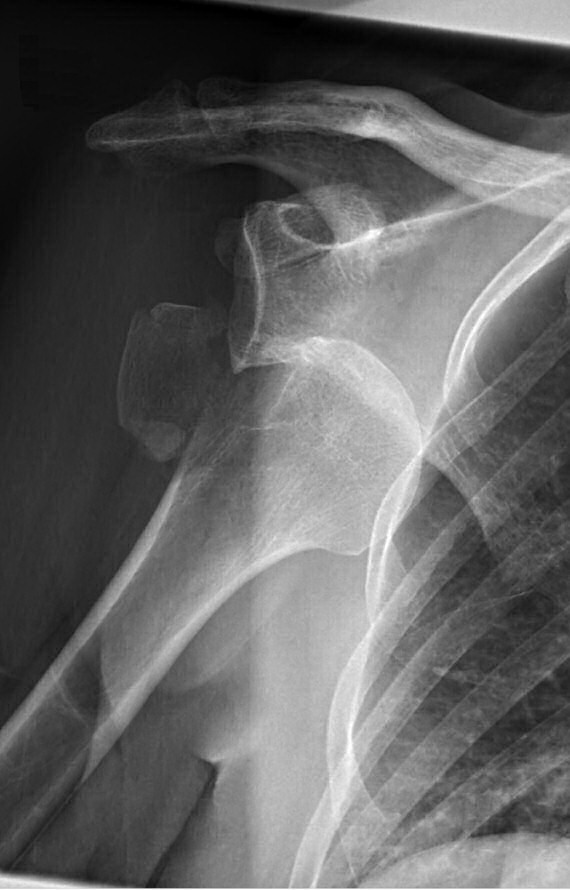

Efter reponering

Axelluxation med avlöst tuberkulum majus innan och efter reponering i narkos. Efter reponering förbättrat läge men även misstänkt bony bankart-skada med litet fragment inferiort om glenoiden.